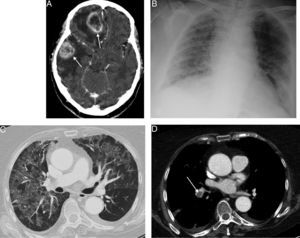

We report the case of a 69-year-old woman with a diagnosis of multifocal GM (Fig. 1A), who presented with a clinical picture of fever and rapidly progressing respiratory failure, 4 weeks after starting temozolomide and high-dose corticosteroids. Chest radiograph (Fig. 1B) showed increased ground glass density in both lungs, which was confirmed on chest computed tomography (CT) (Fig. 1C). An incidental finding was bilateral pulmonary thromboembolism (Fig. 1D). PJP was suspected, so fiberoptic bronchoscopy was performed which confirmed PJP in bronchoalveolar lavage. The patient responded favorably, both clinically and radiologically, to anticoagulants and antibiotic treatment with trimethoprim–sulfamethoxazole.

(A) Axial CT image of the head, after administration of intravenous contrast medium, showing 2 intra-axial ring enhancing lesions (arrows) in the left cerebral hemisphere, with a significant mass effect and associated perilesional edema. (B) Anteroposterior chest radiograph showing ground glass opacities in both lungs. (C) Axial image of chest CT (lung window), showing a noteworthy mosaic pattern in the pulmonary parenchyma, with areas of ground glass attenuation alternating with others of less density, typical of Pneumocystis jirovecii infection. (D) Axial image of chest CT (mediastinum window) with intravenous contrast (obtained at the same level as image C), showing central filling defect in the right lower lobe artery (arrow), associated with pulmonary thromboembolism.